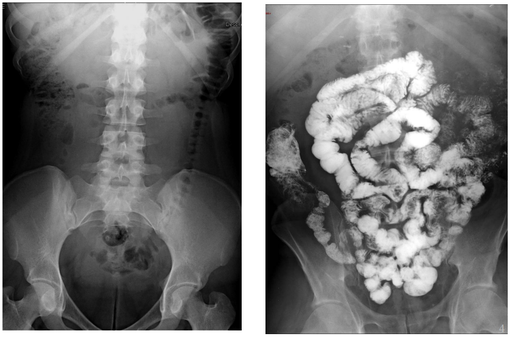

Contraste digestif en radiologie adulte

DANSE E. - UCL

Digestif MASTER 1